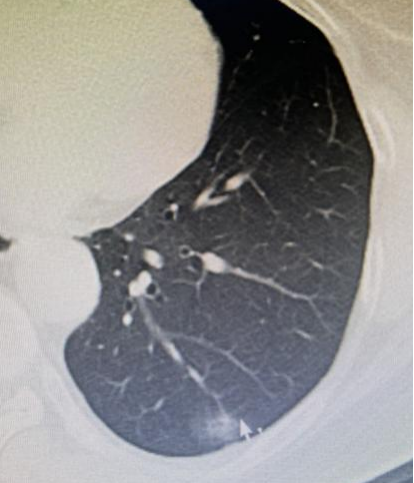

黄阿姨体检发现的位于左下肺的毛玻璃样结节

综合黄阿姨的其他详细情况来看,梁恒星认为这个结节极有可能是早期肺癌。但为了做到精准无误,梁恒星建议黄阿姨密切监测结节增长情况,三个月之内再来复诊。如果结节还是存在,就可以肯定是肺癌无疑。